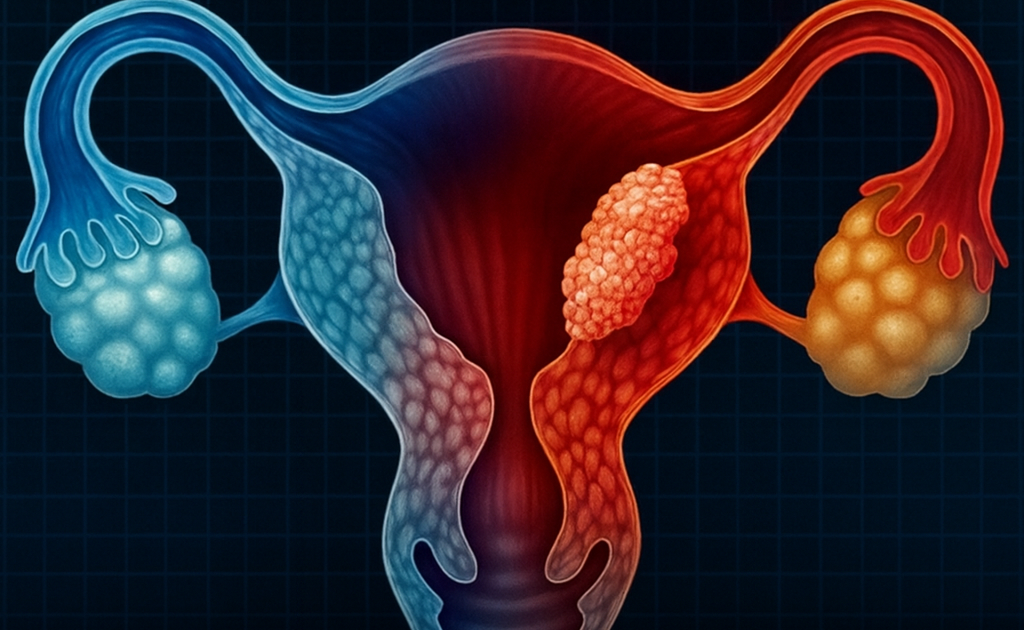

Cervical cancer is often discussed as a “women’s health issue,” but the truth is that certain male behaviors can significantly influence a woman’s risk—especially when it comes to exposure to HPV, the virus responsible for the vast majority of cervical cancer cases.

Although rarely discussed, this practice can have real implications for intimate health. During menstruation, the cervix may be slightly more open, and the body’s natural defenses are temporarily reduced. This creates an easier pathway for viruses or bacteria to enter, including HPV if one of the partners is infected.

It’s not the act itself that causes cervical cancer, but the conditions surrounding it can increase the chance of exposure to infections. Many women prefer to avoid intercourse during this time to reduce unnecessary risks and allow the body to maintain its natural balance.

The chemicals released from tobacco weaken the body’s natural defense systems and disrupt the vaginal microbiome. When this balance is disturbed, the body becomes more vulnerable to infections, including HPV.

Many long-term couples stop using condoms, assuming they are only necessary for preventing pregnancy. But protection plays a crucial role in reducing the transmission of silent infections—those that can linger without symptoms and cause complications later.

HPV is responsible for nearly 95% of cervical cancer cases—but the good news is that the infection can often be prevented through vaccination, condom use, and routine screening tests such as the Pap smear and HPV test.